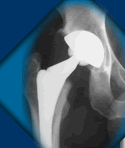

Regarding total hip arthroplasty, one of the most critical technical challenges involves accurate placement of the acetabular

component. Using surgical navigation methods to track the position of the pelvis and the relative position of the acetabular component as it is being implanted is the most reliable method of performing this step of the procedure. Proper acetabular

cup positioning can be challenging because the patient's pelvis

moves around during hip replacement surgery and it's impossible

to know the exact position of the pelvis at the moment that

the acetabular cup is being inserted unless the motion of

the pelvis is tracked during surgery. Even taking xrays during

surgery has limitations because the exact angle of the xray

is not known so precise measurements are difficult to make.

Acetabular component malposition can lead to an increased

likelihood of a number of problems including accelerated wear

of the hip, bone loss around the hip due to the wear debris,

impingement of the components, or dislocation of the hip and

can lead to repeat surgery for any of these problems. Using

computer assistance to measure the position and orientation

of the acetabular cup during its insertion is a very important

application of surgical navigation since improved component

positioning inevitably leads to a lower incidence of all of

these problems.

Computer-assisted surgical navigation of acetabular component implantation involves calculating and tracking the position of the pelvis during surgery and then calculating the position of the prosthetic acetabular component relative to the pelvis as it is being implanted.